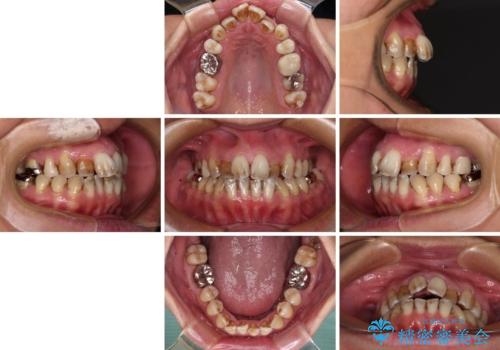

前歯の後戻り インビザラインでの再矯正治療

- かつて抜歯矯正を行ったものの、後戻りをしてしまったとのことで来院された患者様です。

上顎前歯が前突し、隣の歯が裏側に移動してきている状態でした。

飲み込みの状態を確認したところ、舌の突出癖が認められたため、それによる後戻りの可能性が高いと考え、舌のトレーニングを指導しました。